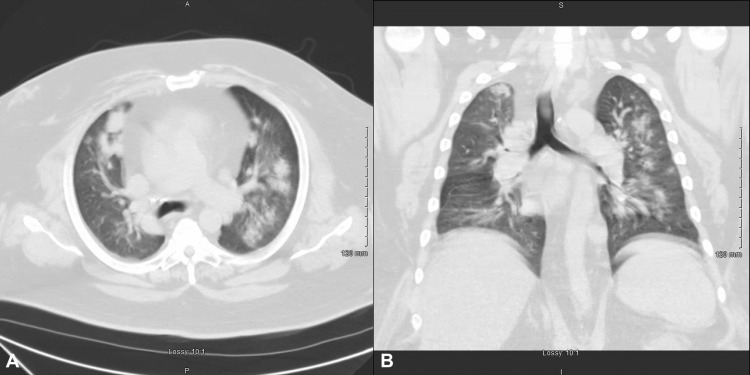

A 51-year-old male with a past medical history of hypertension, heart failure with preserved ejection fraction, severe obstructive sleep apnea, obesity, diabetes mellitus, and hypertension presented to the hospital at the urge of his pulmonologist due to shortness of breath of five days duration and abnormal findings on a chest computed tomography (CT) performed earlier that day. He reported a productive yellow, non-bloody cough. He denied nausea, vomiting, chest pain, abdominal pain, lower extremity edema, and pillow orthopnea. He reported compliance with his nightly bilevel-positive airway pressure ventilation mask. Social history was notable for over 20 years of smoking marijuana in the form of a "blunt" on a daily basis, but denied ingesting edible forms or vaping of any form. The patient also denied alcohol use, tobacco use, and all other drug use. His home medications included oral aspirin 81mg daily, oral simvastatin 20mg daily, oral metformin 1000mg twice daily, oral glipizide 10mg twice daily, oral sitagliptin 100mg daily, oral furosemide 40mg as needed, oral enalapril 20mg twice daily, and oral carvedilol 25mg twice daily. Initial vital signs: temperature of 98.9 F, blood pressure of 165/95 mmHg, pulse rate of 91, respiratory rate of 20, and oxygen saturation of 96% on 3L low flow supplemental oxygen. Physical exam was unremarkable except for bilateral wheezing and large body habitus. A chest CT obtained earlier in the day demonstrated bilateral patchy and nodular airspace infiltrates and cardiomegaly (Figure 1).

In our patient’s case, we identified marijuana smoking as the etiology for his lung injury pattern based on a thorough diagnostic workup. Previous reports have described symptomatic marijuana-induced lung injury as a disease entity, satisfying criteria one and two. We ruled out autoimmune and infectious etiologies for the patient’s clinical manifestations through an extensive workup as detailed in the case presentation, satisfying criterion three. Additionally, since the patient’s symptoms resolved and never relapsed following discontinuation of marijuana smoking, criterion four is met. We are unable to satisfy criterion five, as it would have been unethical to administer a medication that has the potential to cause patient harm. One study by Yamauchi et al. examined the BAL cytology of patients with drug-induced pneumonitis. The study found that, in patients with DLI, the most common BAL finding was elevated lymphocyte cell fractions [ref. 9]. Consistent with this study, our patient’s BAL cytology also showed an elevated lymphocyte cell fraction, suggestive of DLI. Interestingly, the chest CT of our patient demonstrates diffuse bilateral patchy opacifications and similarities resembling what He et al. describe as a "tree-in-bloom" [ref. 5]. This "tree-in-bloom" appearance may be a radiologic pattern that some patients with marijuana-induced lung injury exhibit and warrants further study.

Marijuana, also commonly referred to as cannabis, is a commonly abused illicit substance that has gained worldwide popularity. Due to its common use, we believe marijuana-induced lung injury is a diagnosis that may increase in prevalence in the coming years. Its ability to produce a significant disease burden to patients requires further studies as it has only been previously reported in case studies. Consistent with other studies, we identified elevated lymphocyte cell fractions in our BAL and noted patchy opacifications with a "tree-in-bloom" pattern on chest CT. Clinicians should consider marijuana-induced lung injury in patients presenting with diffuse pulmonary opacifications after ruling out infectious and autoimmune etiologies. We aim to increase awareness of this pulmonary pathology by describing a unique patient case and sharing our radiologic, bronchoscopic, and laboratory findings.